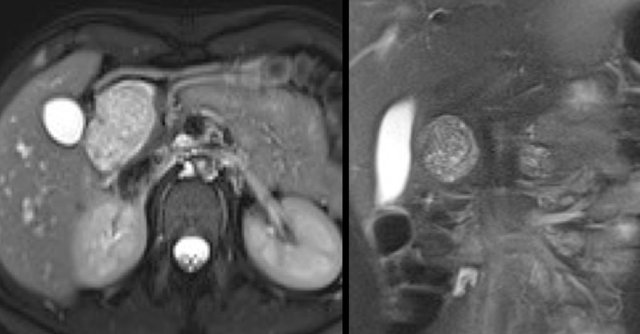

CT-image of a 51 year old woman with a history of gallstones and abdominal pain.

There is a hypodense lesion with central calcification in the head of the pancreas.

The lesion has a lobulated contour.

Continue with the MR.

MRI better demonstrates the morphologic features of the lesion (fig).

On T2WI the lesion is multicystic.

Note the central low signal due to the central scar with calcifications.

Although some of the cysts are rather large, this is still a characteristic appearance of a serous cystic adenoma (macrocystic form).